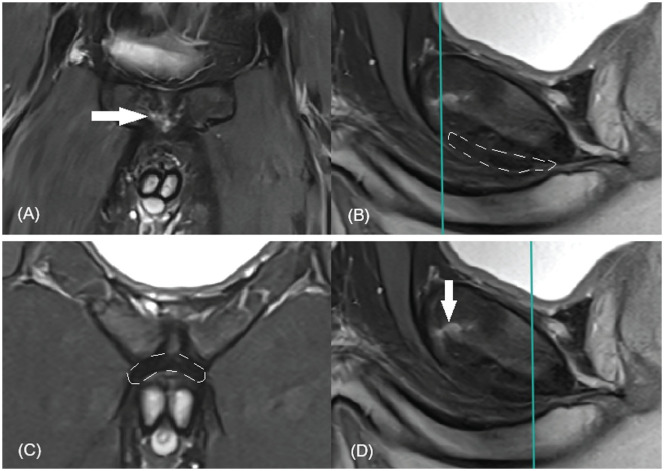

Abstract Image